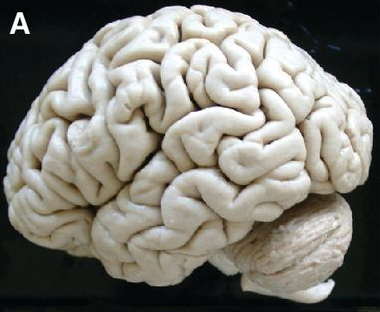

| Preserved human brain, 65-year old female.

| Brain surface

- Show Big Brain 400 um volume surface rendered.

- Move around with space navigator and leap motion. Let everyone try.